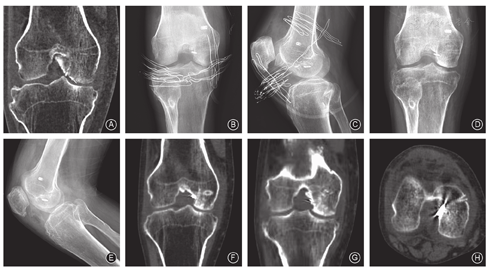

关节镜下手术:全身麻醉联合股神经阻滞,患者平卧位,患肢扎气囊止血带。膝关节屈曲90°,取前内、前外侧入路,置入关节镜及刨刀清理后十字韧带及撕脱骨块周围的软组织,探及后十字韧带松弛。撕脱骨块向髁间窝移位,大小约2.0 cm×2.5 cm,其中约4 mm×4 mm面积与股骨内侧外侧壁畸形愈合。使用刨刀及交换棒去除骨痂,使撕脱骨块游离。清理骨床,彻底清除嵌顿于骨块与骨床间的滑膜、纤维组织、破碎骨块、血凝块。采用分段钻孔的方法:(1)以交换棒推挤骨块至骨床内,以4.5 mm骨钻在撕脱骨块中央打孔;(2)将后十字韧带股骨定位瞄准器(ACUFEX,Smith & Nephew,美国)尖端固定于骨床中央,由股骨前内侧向骨床内打入2.0 mm克氏针并以4.5 mm空心钻扩孔。拔出克氏针,引入PDS-Ⅱ缝线作牵引线,将带襻钛板由前内侧入路带入关节腔,使襻环牵引线依次穿过骨块、股骨隧道,至襻钛板紧贴撕脱骨块。拉紧襻环牵引线,凭借襻钛板的横截面将撕脱骨块压至骨床内解剖复位,用6 mm界面螺钉(Smith & Nephew,美国)将襻环挤压固定在股骨隧道内(图3)。手术时间55 min,术中无血管、神经损伤,术后无切口感染、液体外渗及血肿等。

术后X线、CT扫描及三维重建示骨折解剖复位且维持良好(图4)。术后3个月随访时患者膝关节运动范围为0°-120°、Lysholm功能评分89分,可正常行走,但无法从事高强度体育锻炼。厚皮性骨膜病病情平稳,无明显进展。